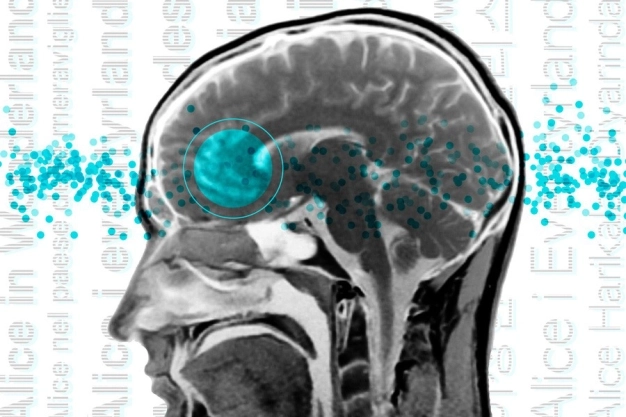

İster Türkçe ister Norveççe konuşun beynin dil ağı aynıSinir bilimciler, beynin dil ağının yani beynin dili işlemek için uzmanlaşmış bölgelerinin iyi tanımlanmış bir haritasını geçen yüzyılın sonunda oluşturdu. Esas olarak sol lobda bulunan bu ağ, Broca alanı içindeki bölgelerin yanı sıra ön ve şakak loblarının diğer kısımlarını da içeriyor. Ancak, bu haritalama çalışmalarının büyük çoğunluğu İngilizce konuşanlar tarafından İngilizce metinleri dinlerken veya okurken yapılmıştı. Yani tek bir dil ile sınırlıydı.

Massachusetts Teknoloji Enstitüsü nörobilimcileri, şimdi 45 farklı dili konuşanların beyin görüntüleme çalışmalarını gerçekleştirdi. Sonuçlar, konuşmacıların dil ağlarının anadili İngilizce olanlarla aynı olduğunu gösteriyor.

Beyindeki dil ağının, konumunun ve temel özelliklerinin evrensel olduğunu ortaya koyan bulgular şaşırtıcı olsa da bu sonuçlar hiçbir fark olmadığı anlamına da gelmiyor. Örneğin İngilizce, diğer dillerde yaygın olarak görülen birçok özelliği içermiyor. İngilizce’de sözcük sırası sabit olma eğilimindeyken, diğer dillerde sözcüklerin sıralanma biçiminde daha fazla esneklik bulunuyor. Bu dillerin çoğu, kelimeler arasındaki ek anlam ve ilişkileri iletmek için morfemlerin veya kelime segmentlerinin eklenmesini kullanıyor. Elde edilen bulgular ışığında, farklı dilleri konuşanların kodlamalarının işitsel beyin bölgelerinde daha güçlü bağlantıları olan bir dil ağına sahip olup olmadıkları da araştırılıyor.